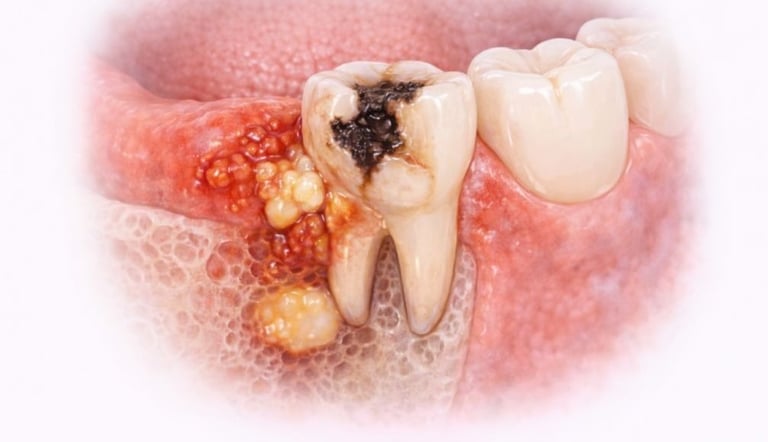

When Is Tooth Extraction Needed?

Tooth extraction may be recommended in cases of:

Severe tooth decay or infection

Broken or fractured tooth beyond repair

All images shown here represent real clinical cases of teeth extractions done at our dental clinic with patient consent.

Illustrative images and similar real clinical cases requiring tooth extraction

Q7. Can a badly damaged or decayed tooth be saved instead of removed?

In some cases, root canal treatment or restorative procedures can save the tooth. However, if the tooth is severely damaged or infected, extraction may be the safest option.

Q8. Do you use X-rays before tooth extraction?

Yes, dental X-rays are taken before extraction to assess the tooth position, root structure, and surrounding bone, ensuring safe and precise treatment.